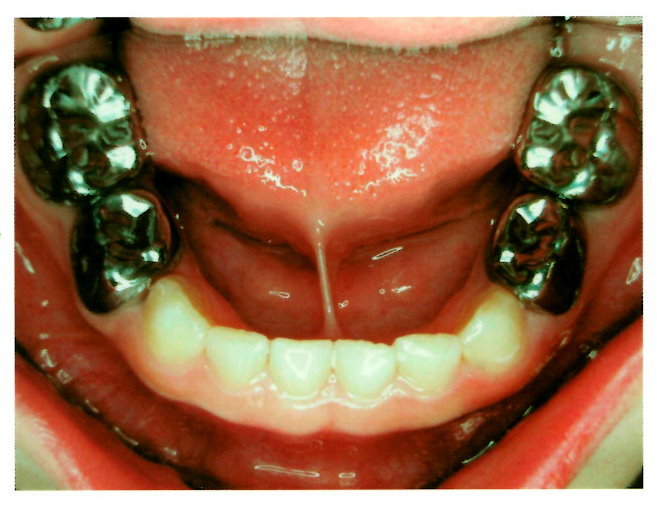

不锈鋼牙冠重建

乳牙若已完成根管治療,建議以不銹鋼牙冠重建齒質,除了可以保有原有的咀嚼功能之外,亦可有維持空間的功能。